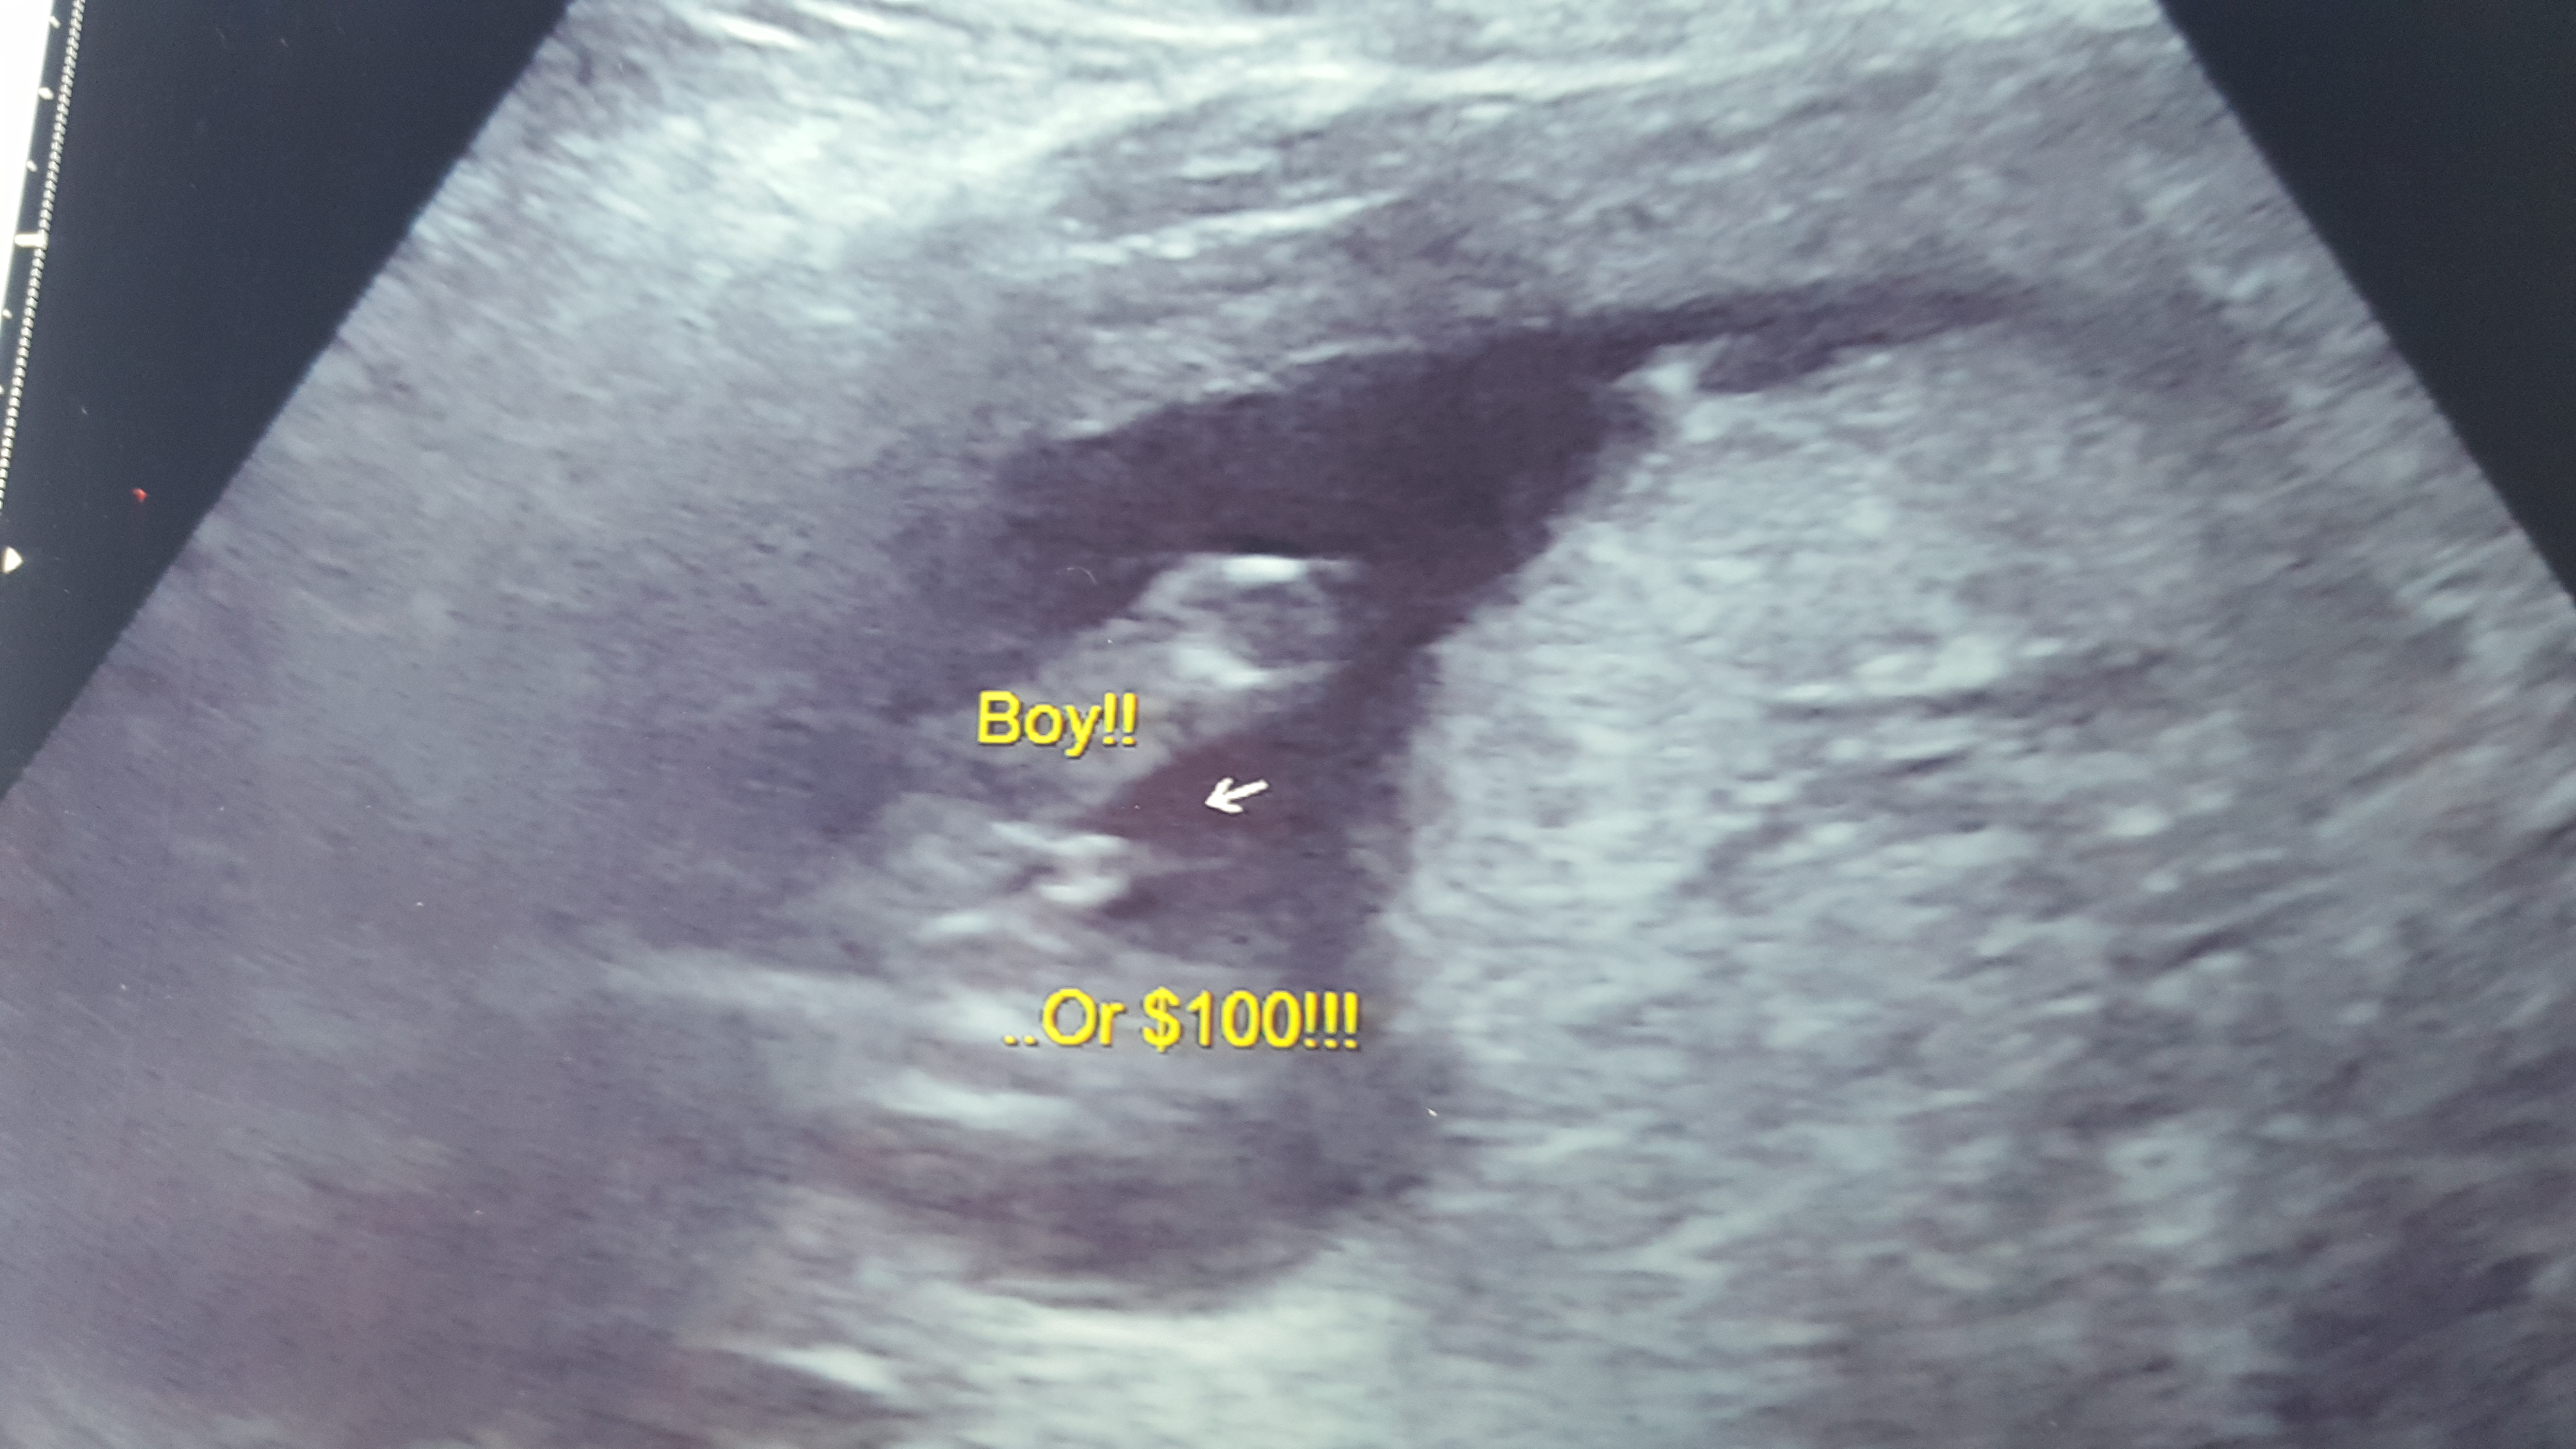

Is this a boy for sure?!

I went to a elective ultrasound at 15 weeks and the tech said boy or id get my money back ($100). Im sure he is right but this pic makes me think twice since i know girl parts can be swollen at this stage too. Attachment 29065 Would do you all think?